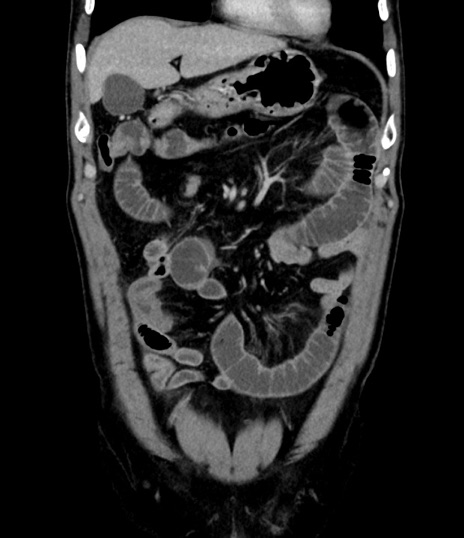

症例8(冠状断像)

【症例】 60歳代男性

【主訴】 黒色吐物

【現病歴】 4日前から嘔気自覚、2日前の朝食後にも嘔気あり、自分で手で嘔吐反射起こし嘔吐したところ血が混ざっていたため受診。

【既往歴】 5年前汎発性腹膜炎を伴う急性虫垂炎で手術、高血圧、前立腺肥大症、高脂血症

【身体所見】 腹部正中に手術癩痕あり 腹部平坦・軟圧痛なし膨満感あり

【データ】WBC 8400、CRP 4.54